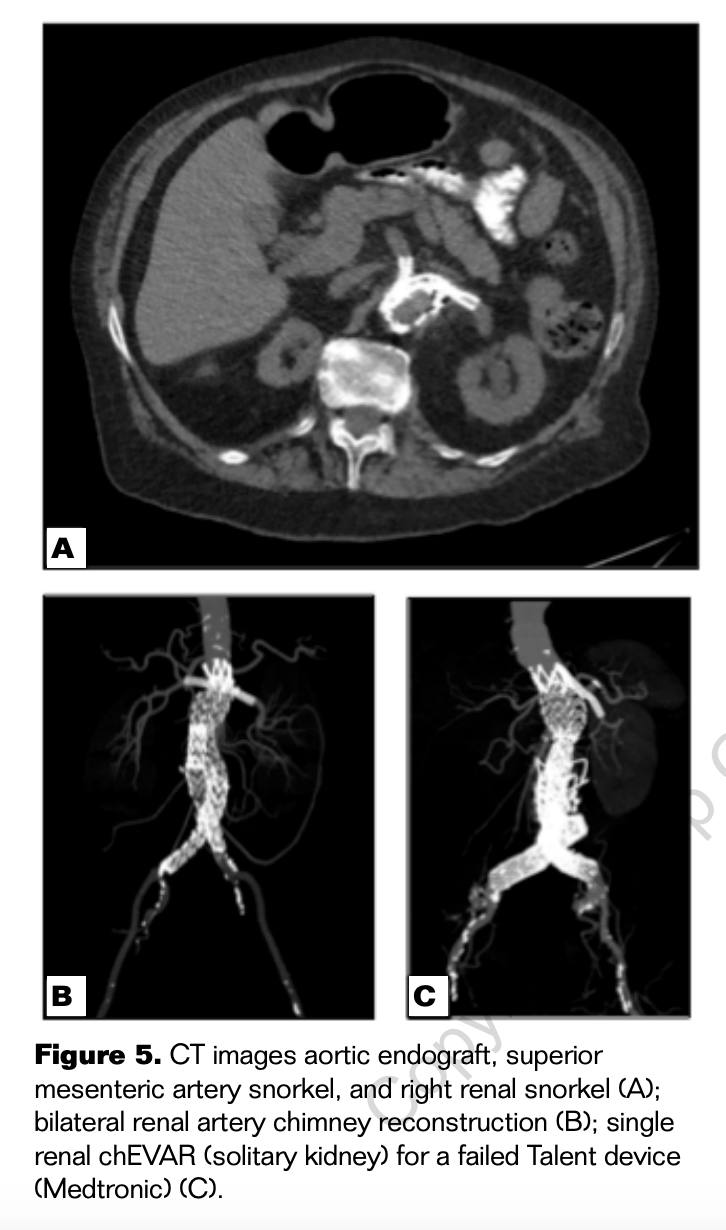

The potential advantage of the chEVAR technique using devices designed with suprarenal fixation is that it separates the potentially compromised fixation and seal that occur using this technique. The chimney stents can be specifically placed above the fabric of the device, but below the fixation, so that fixation is not compromised (Figures 2 and 3). This technical aspect still allows for potential “gutter” endoleaks, but will likely minimize the risk of migration. Micro and standard computed tomography (CT) scan imaging have demonstrated the successful interaction between the chimney stents and an endograft with suprarenal fixation (Figures 4 and 5). The above data from the registries and micro and standard CT scan imaging confirm the efficacy of this technique with suprarenal fixation.